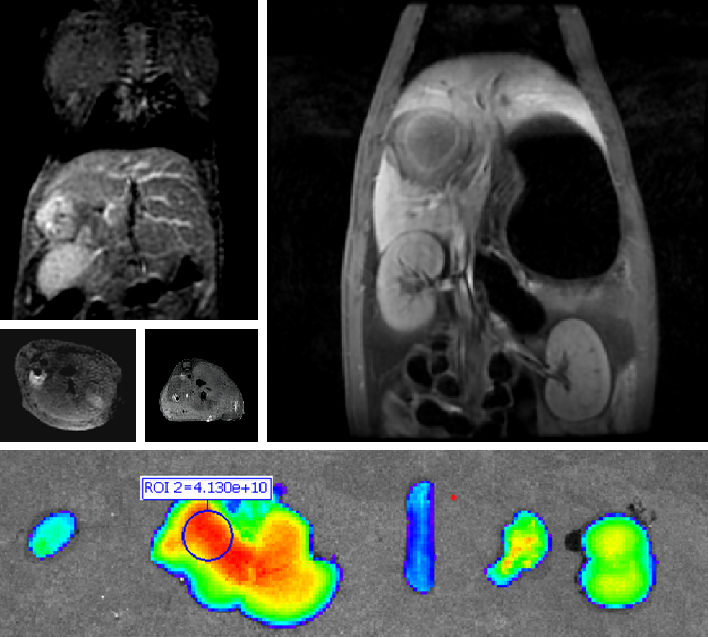

PL002是浙江普利藥業(yè)有限公司研發(fā)的熒光/磁共振雙模態(tài)造影劑,開發(fā)熒光/磁共振雙模態(tài)造影劑成為提高原發(fā)性肝癌手術(shù)效率的有效方案。雙模態(tài)造影劑的熒光成像能力可用于肝癌術(shù)中熒光導(dǎo)航,而磁共振增強能力可用于在術(shù)前判斷肝臟代謝能力,推測腫瘤及肝臟對造影劑的攝取情況,提高腫瘤診斷精度,降低術(shù)前規(guī)劃難度。

PL002相較于吲哚菁綠具有明顯優(yōu)勢。目前吲哚菁綠在臨床使用中存在給藥到手術(shù)時間不確定的問題,可能造成病灶與正常組織對比度不足,影響術(shù)中的病灶的判斷,PL002采用獨特的釓絡(luò)合物與熒光分子共價鍵結(jié)合的分子結(jié)構(gòu)設(shè)計,這種設(shè)計能夠讓醫(yī)生在術(shù)前通過磁共振成像確定造影劑在病灶中的聚集情況,進而針對患者個體情況來對手術(shù)時間進行規(guī)劃。同時,由于PL002體內(nèi)更為穩(wěn)定,在荷瘤小鼠模型中同等條件下熒光成像效果維持時間長于現(xiàn)有熒光造影劑,也保證了其在臨床應(yīng)用中具有更寬的手術(shù)窗口。